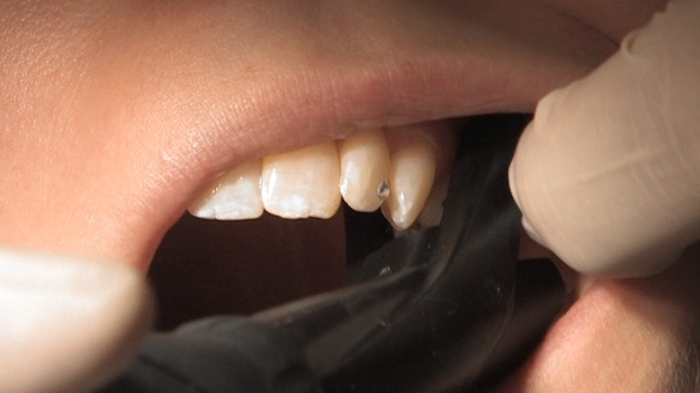

Изображение на DIAGNOcam получается благодаря технологи DIFOTI (цифровая фиброоптическая трансиллюминация). Прибор генерирует лазерное излучение в нерентгеновском диапазоне волн. При этом через здоровую часть зуба луч проходит свободно, без препятствий, а непроницаемые области, такие, как кариес, легко обнаруживаются и представляют собой затемненные на общем фоне участки.

Встроенная видеокамера передает изображение на экран в режиме реального времени. Таким образом, благодаря отсутствию излучения данную процедуру (диагностика кариеса) можно повторять настолько часто, насколько это необходимо. Это очень удобно, особенно для детей, беременных женщин и пациентов с противопоказаниями к рентгеновским методам исследования.

Кариес выявлен при помощи метода DIFOTI (инструмент DIAGNOcam). В этом случае клинических данных недостаточно для выявления кариозного поражения.